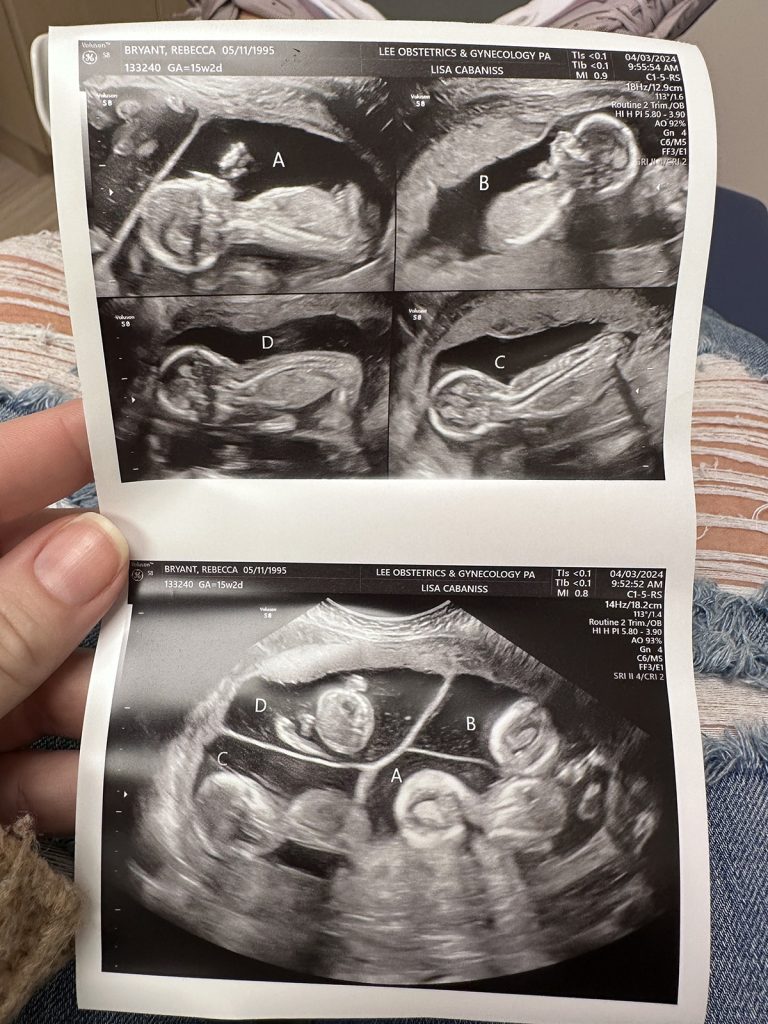

In February 2024, Becca and Lavareis Bryant attended a routine ultrasound appointment in their hometown of Auburn, Alabama. With three older children, the couple was excited to get their first glance at their fourth baby. They were also nervous as they had recently experienced a miscarriage.

“The ultrasound tech started moving the machine around, and I started to notice one big spot and two smaller ones,” Lavareis said. “The next thing I know, she’s counting — 1 … 2 … 3 … 4!”

They stared at each other in disbelief. The final baby of the family was actually four babies. Becca’s pregnancy was now considered high-risk. Her obstetrician referred her to the UAB maternal-fetal medicine team, who specializes in high-risk obstetrics and unique pregnancies.

Multiple pregnancies are rare, with twins occurring in one in 80 and quadruplets occurring in one in 700,000. Becca had a trichorionic quadra-amniotic pregnancy, meaning there were four babies and four sacs but only three placentas.

“The odds of this specific type of quads are around one in 7 million,” said Ayodeji Sanusi, M.D., Becca’s maternal-fetal medicine physician at UAB. “Three eggs were fertilized; but one split, making two of the babies identical and two fraternal. It also added on to the complex and high-risk nature of her pregnancy.”